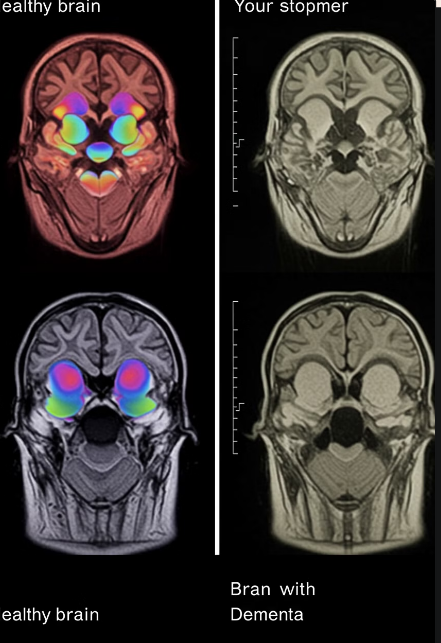

치매는 단순한 노화 현상이 아니라 뇌 기능이 저하되어 기억력, 판단력, 언어 능력 등 여러 인지 기능이 지속적으로 감소하는 질환입니다.